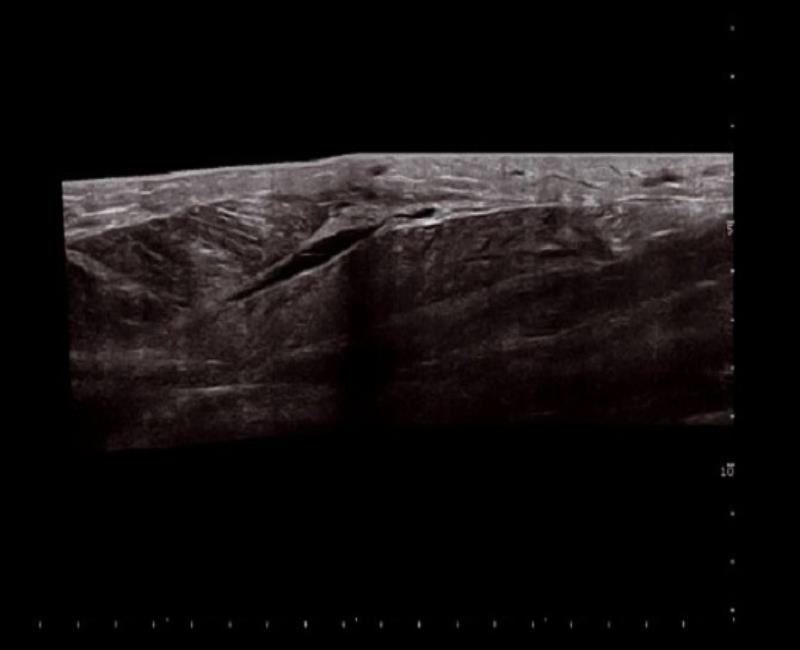

VPAN - mở rộng trường nhìn trên đầu dò Linea lên đến 60 cm.